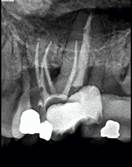

Radiografía de seguimiento a los 6 meses mostrando signos de curación.